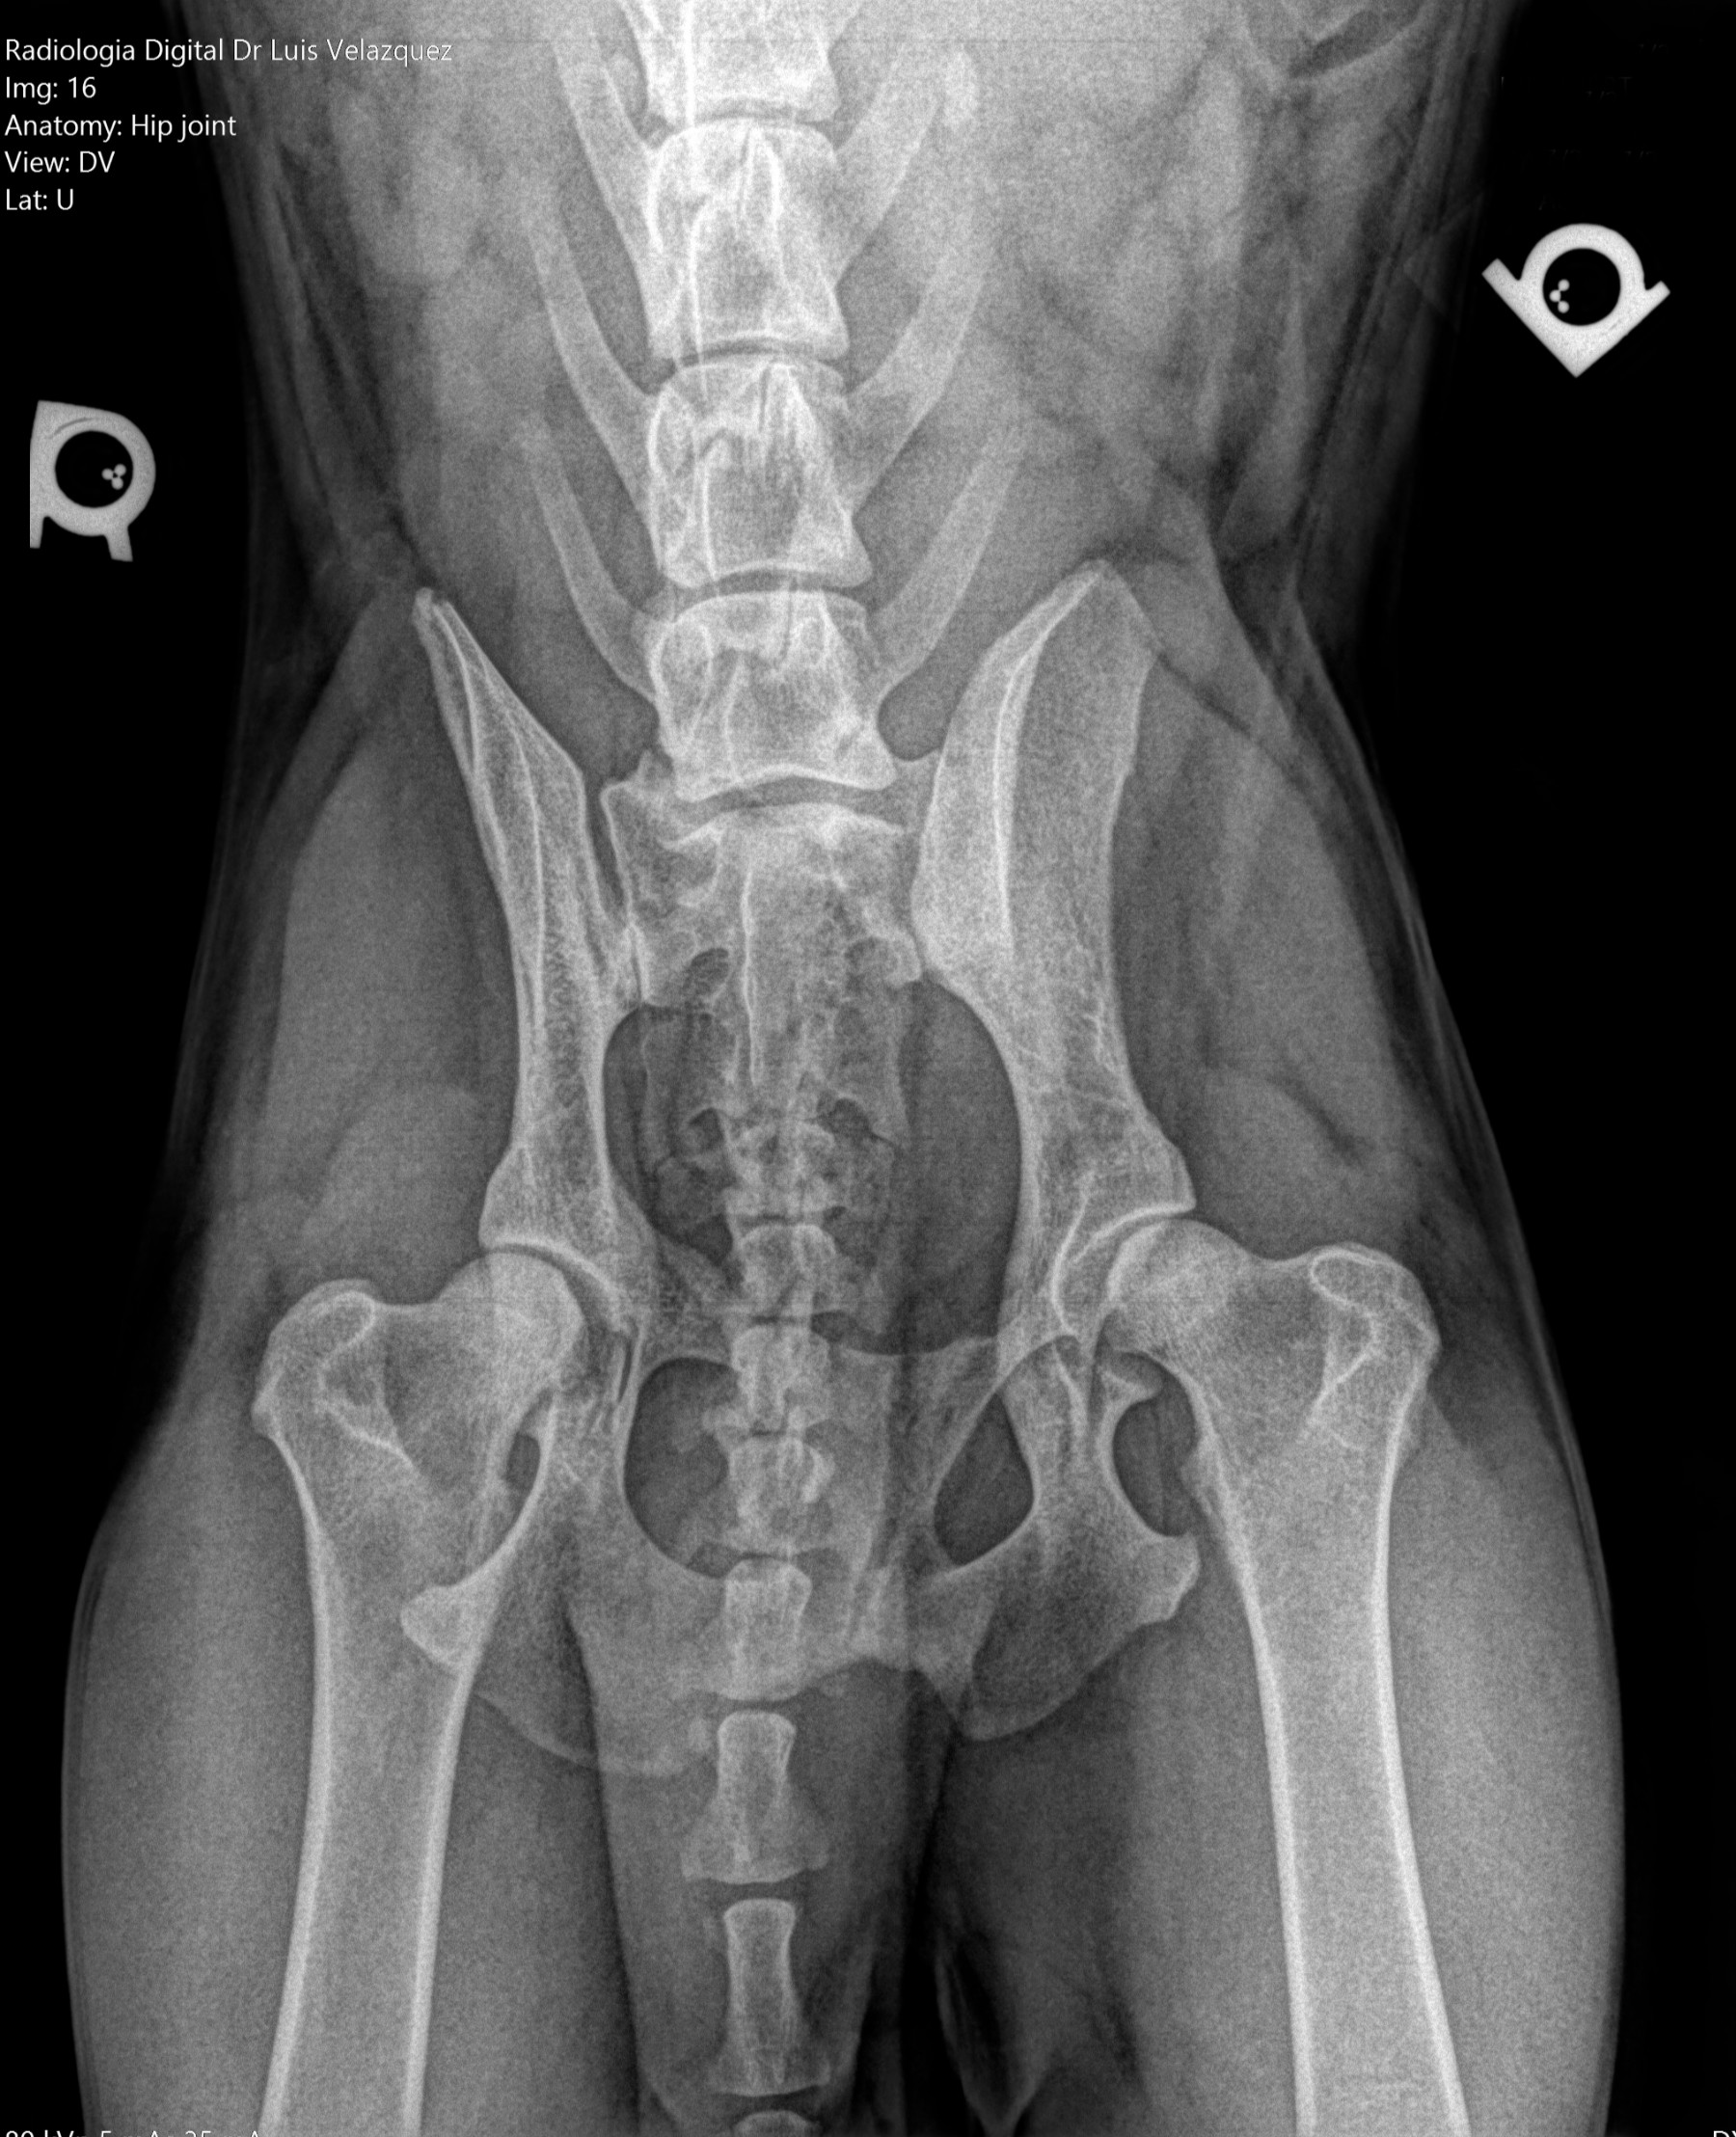

Cambios Térmicos en las Extremidades de Caballos,

Asociados a Golpes y su Evaluación por Termografía.

Los caballos de salto, en competencia, pueden derribar obstáculos y lastimarse. Si se golpean, no siempre claudican. Considerando al calor como un signo de inflamación, se evaluaron los cambios térmicos de 6 áreas de las extremidades torácicas y pelvianas de 23 caballos de salto en nivel de competencia de 1.05 a 1.60 m de altura, por medio de termografía durante 4 días de competencia (N=2208 áreas).